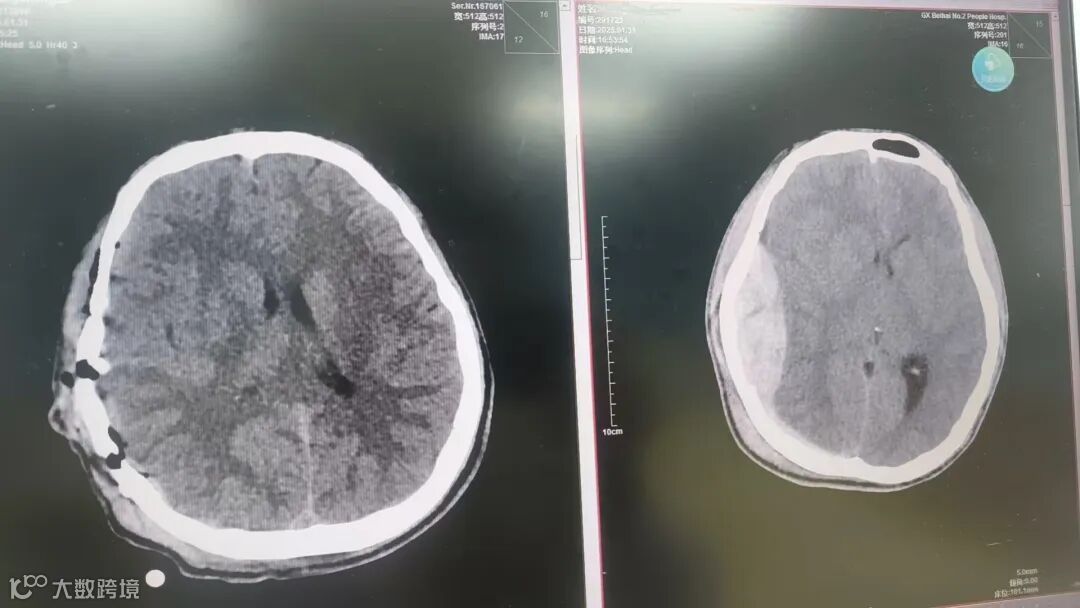

17时45分入手术室,麻醉与手术团队很快做好准备,神经外科医生胡亮主刀,采用右侧额颞部入路,行“开颅血肿清除+去颅骨骨瓣减压术”,仅22分钟便完成开颅减压过程。脑压减压充分,有很大机会保留骨瓣,遂行开颅硬膜外血肿清除术。

21时30分手术灯熄灭,监护仪显示患者生命体征平稳,患者术前散大的瞳孔恢复正常。经过3个多小时手术救治,这个17岁的鲜活生命保住了!